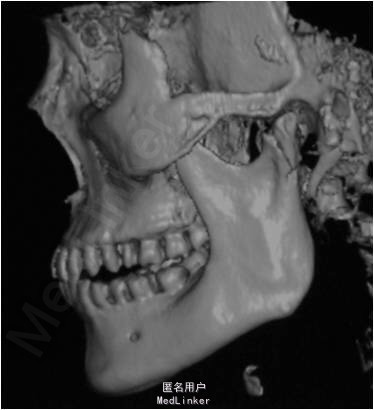

颏部可见擦伤,其余部位未见明显外伤。曲面断层和CT提示,左侧髁突骨质连续性中断

术后髁突愈合良好